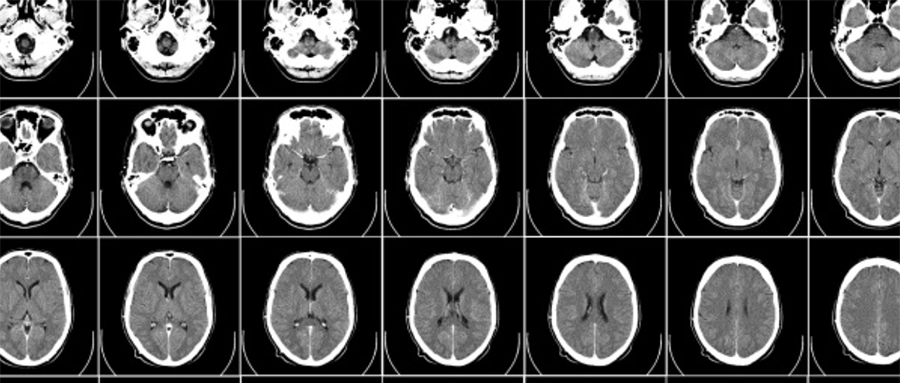

伦敦国王学院研究人员兼伦敦AI中心CTO Jorge Cardoso发现了一种利用AI创建人脑真实3D图像的方法,并使用NVIDIA Cambridge-1超级计算机和MONAI打造了全球最大的开源合成大脑图像集。

该数据集将为医疗健康研究人员免费提供10万张合成大脑图像,以加速人类对痴呆症、帕金森症或各类脑部疾病的认知。

Cardoso的AI方法可以根据需要制作图像。女性大脑、男性大脑、老年人的大脑、年轻人的大脑等等,只需插入所需内容,系统就会进行创建。这些图像虽然是模拟生成的,但非常实用,它们基于经过良好测试的算法,所以外观和运作方式与真实大脑高度相似。

英国健康数据研究所作为国家级资源库,将托管10万张大脑图像。Cardoso还希望提供他的AI模型,以便研究人员创建所需的图像。其团队也在探索这些模型如何在医学成像模式下(MRI、CAT、PET等)为人体任意部位生成3D图像。